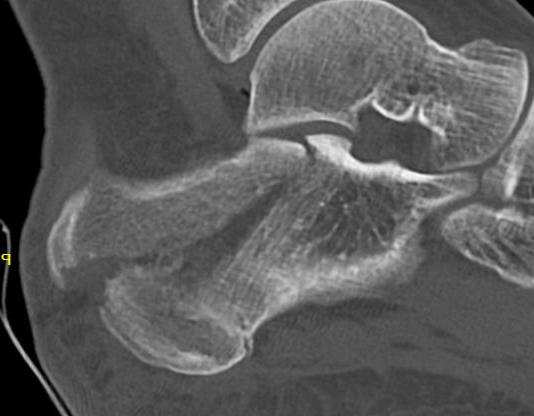

Tongue type

- involve posterior subtalar joint

- secondary fracture line extends posteriorly into calcaneal tuberosity

Imaging